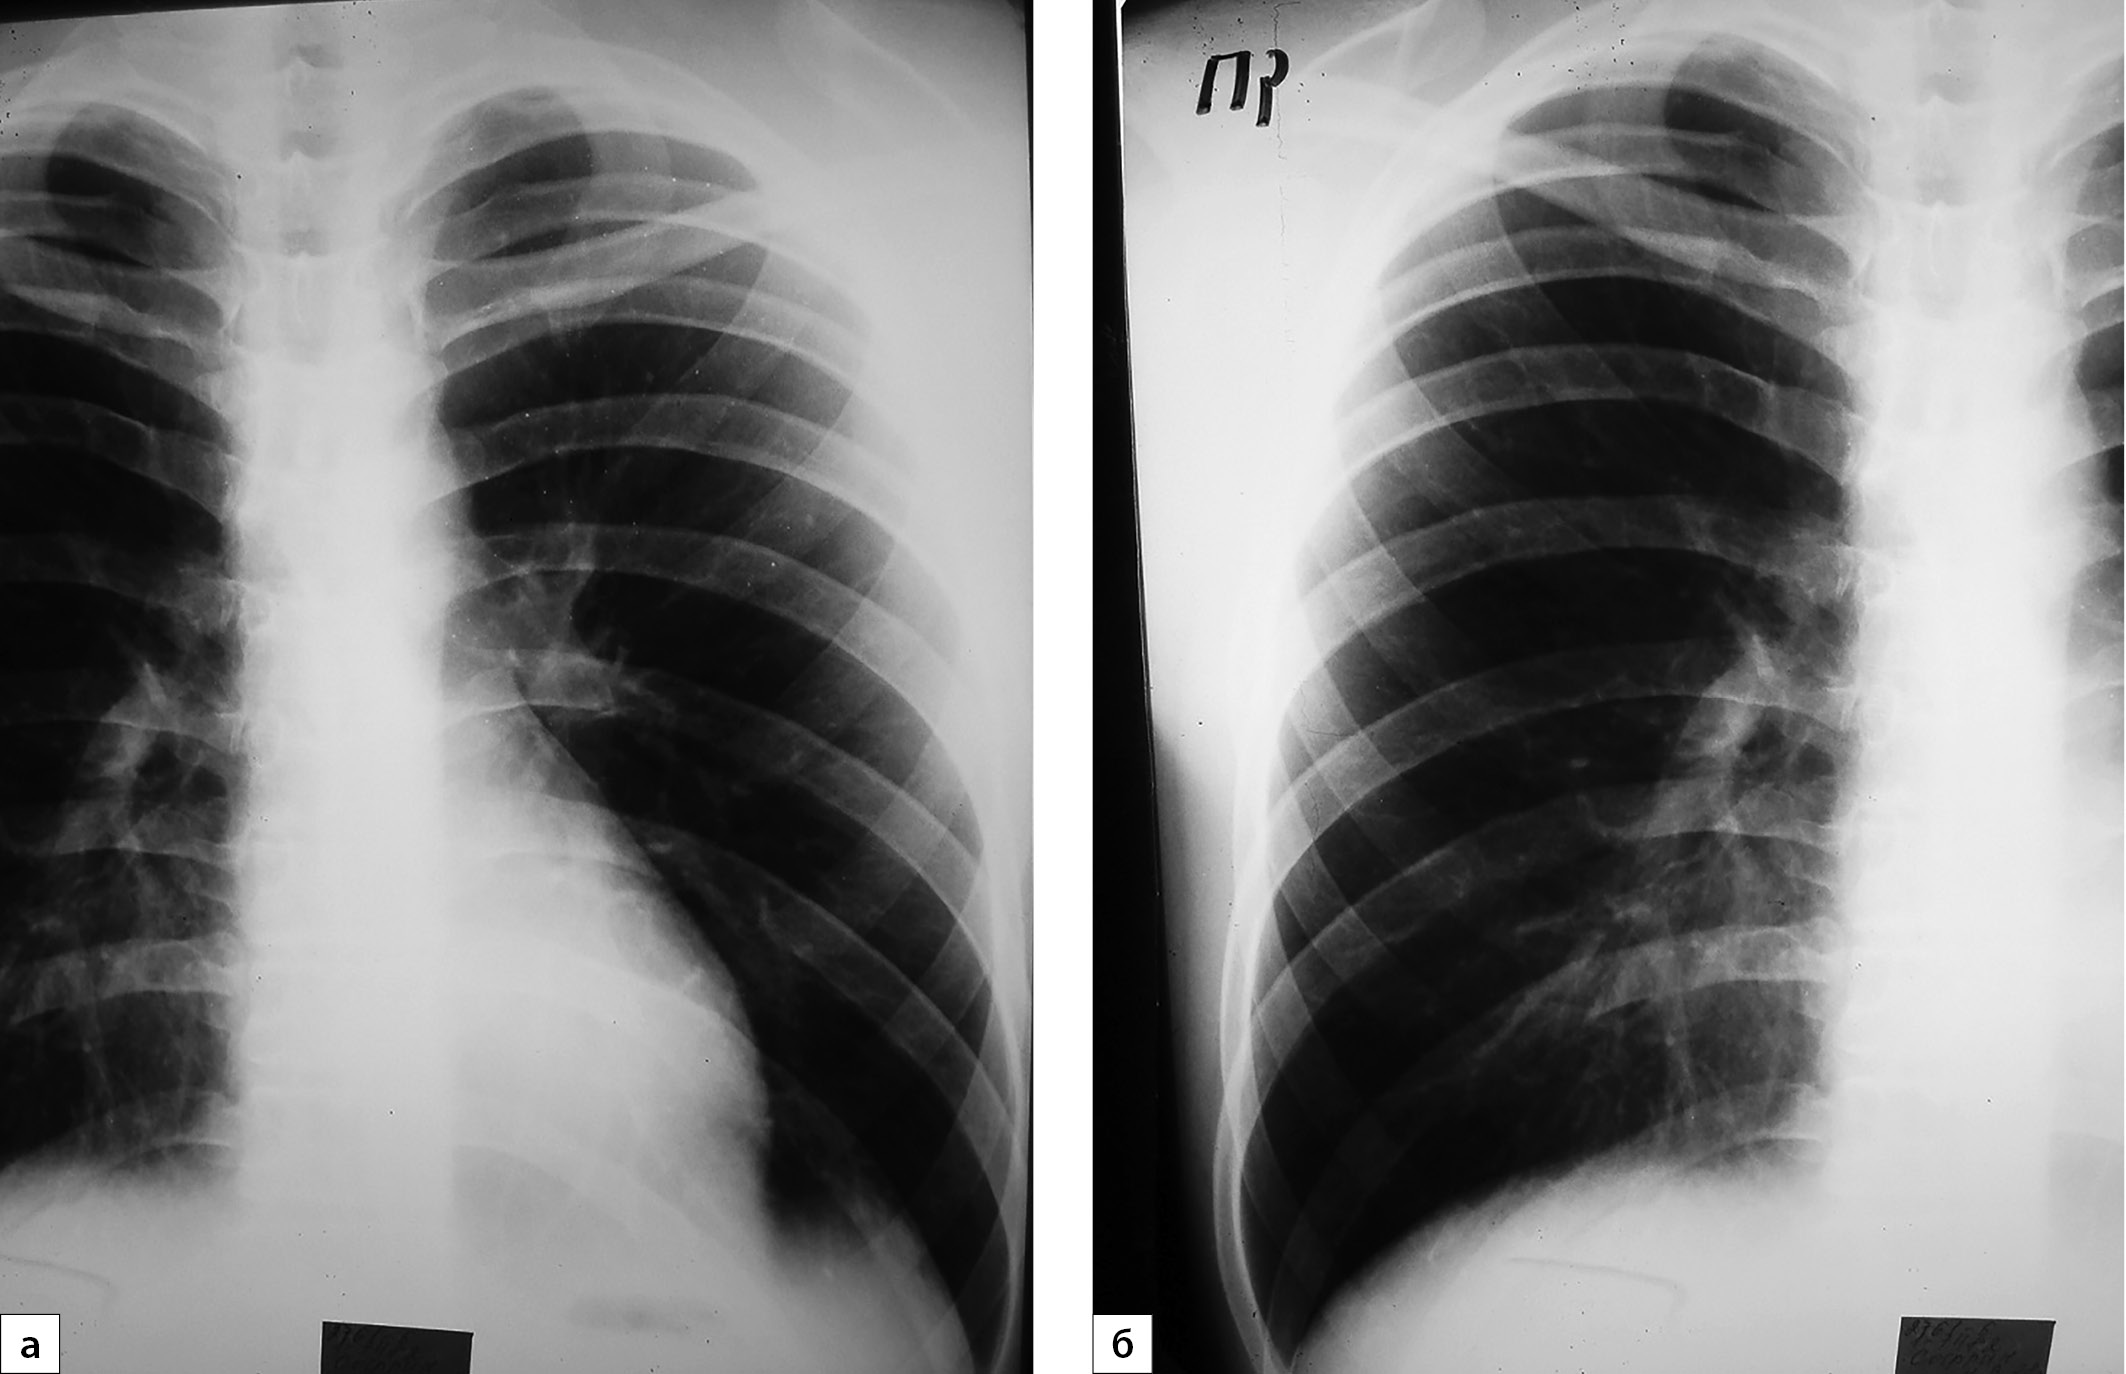

6. Рисунок 6 (а, б). Обзорные рентгенограммы органов грудной клетки в динамике. | |

Тема | ||

Тип | Исследовательские инструменты | |

Посмотреть

(266KB)

|

Метаданные ▾ |